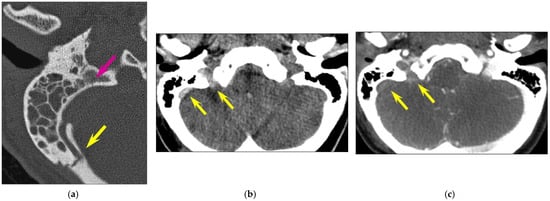

In 22 fractures (22/126, 17.5%), the fracture line involved the carotid canal, but only one case (1/126, 0.8% of all temporal bone fractures; 1/22, 4.5% of fractures involving the carotid canal) showed associated focal internal carotid artery dissection. In 23 cases (23/126, 18.3%), the fracture line extended to the sigmoid groove of the petrous temporal bone; thrombosis of the sigmoid sinus (Figure 4) was present in 4 cases (4/126, 3.2% of all temporal bone fractures; 4/23, 17.4% of fractures involving the sigmoid groove).

A study found that 3.4% of head injuries were associated with petrous temporal bone fractures [22]. The reported incidence of dural venous thrombosis in association with temporal bone fracture, more so with those crossing the dural sinus or jugular bulb, is about 40.7% [25]. When the fracture involves the petrous portion of the temporal bone, the reported incidence of dural venous thrombosis is 22.4% [26]. In our study, the incidence of dural venous thrombosis was 17.4% in fractures involving the sigmoid groove of the petrous temporal bone. It is worth mentioning that no venous thrombosis was detected via CT whenever the fracture line did not involve the sigmoid groove. We had also one internal carotid dissection in an adult (0.8% of all temporal bone fractures and 4.5% of fractures involving the carotid canal). Internal carotid artery injury is reported to occur in 1% of all adult patients with severe head trauma [27] and in up to 9.4% of patients with petrous temporal bone fractures [28]. Complications include hemorrhage, pseudoaneurysm formation, carotid cavernous fistula, stroke and death, with a reported in-hospital mortality rate of up to 45.5% [28]. According to some authors, in adult patients with petrous temporal bone fractures, factors clearly associated with internal carotid artery injury include carotid canal fractures and motor vehicle or motorbike crashes as trauma mechanisms [28]. As these patients have an increased risk of internal carotid injury, some authors have recommended routine screening for internal carotid artery injury using CT angiography [28]. Internal carotid artery injury is only rarely seen in the pediatric population, and data are limited to isolated case reports. Nevertheless, for cranial trauma in children, fractures of the petrous temporal bone or through the carotid canal have been shown to be independent factors for blunt cerebrovascular injury [29].

Figure 4. Vascular injuries. Longitudinal fracture of the right temporal bone and venous thrombosis in a 30-year-old woman involved in a motorway traffic accident. CT of the posterior fossa (a,b) unenhanced CT; (c): intravenous contrast-enhanced CT. (a) A detached fragment of the posterior part of the temporal bone, projecting into the sigmoid sinus (yellow arrow); the fracture line is also seen more medially (pink arrow). (b): spontaneous hyperdensity of the sigmoid sinus and of the jugular foramen (yellow arrows). (c) The absence of the opacification of these vascular structures, consistent with venous thrombosis (yellow arrows).